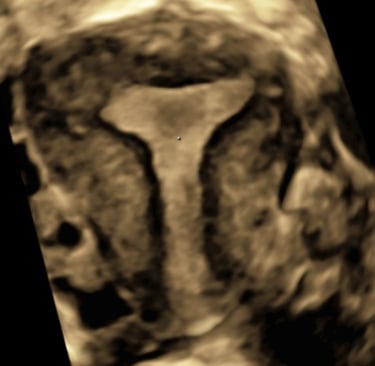

Lors d’une grossesse, l’échographie est un outil indispensable pour le suivi.

Il s’agit d’un examen de dépistage et non d’un diagnostic.